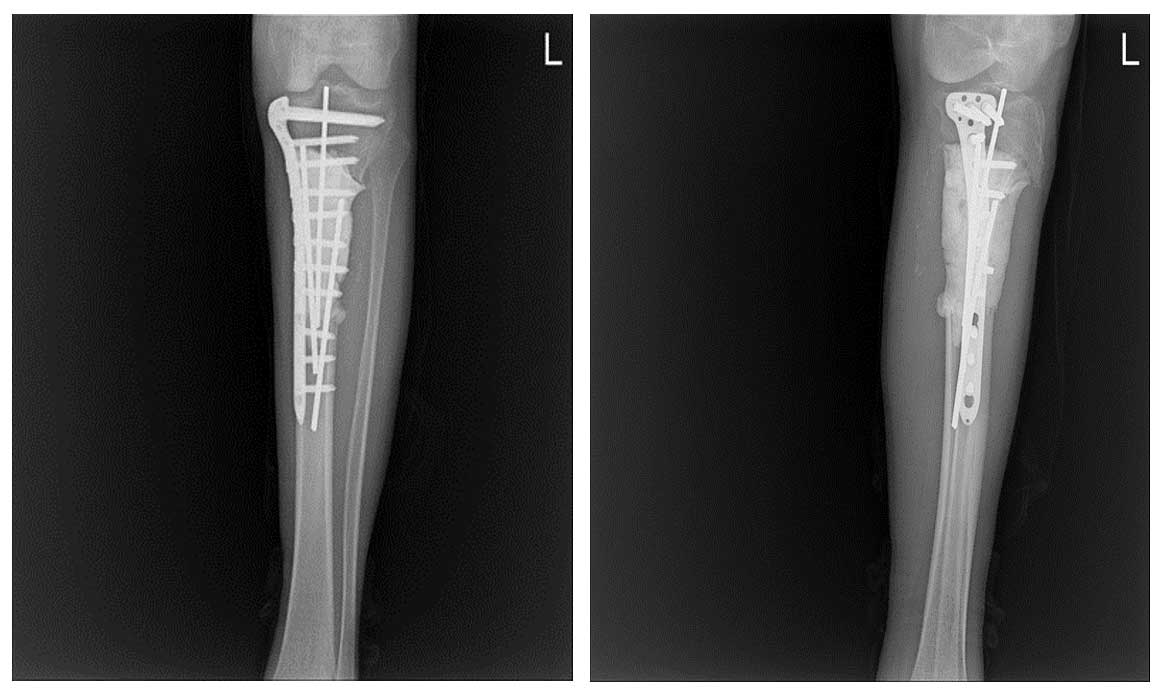

Ameliyat Öncesi: Röntgende sol tibia üst uçta kemikte harabiyet ve ayrışmamış kırık, MR’da aynı bölgede tümör dokusu ve çevreleyen ödem görülmekte.

Ameliyat Esnası: Kemiğin tümörlü kısmının çıkarılması, oluşan boşluğun teller ve kemik çimentosu ile doldurulması ve titanyum plak uygulaması görülmekte.

Ameliyat Sonrası: Kemiğin tümörlü kısmının çıkarılması sonrası oluşan boşluğun teller ve kemik çimentosu ile doldurulması ve titanyum plak uygulaması görülmekte.